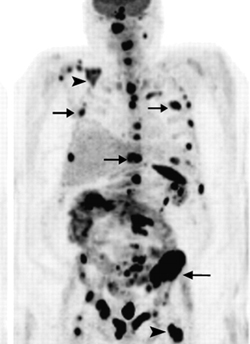

Studiul lui Elise Bassin nu este singurul care arată legătura între fluor şi creşterea riscului de cancer. În 1990, Programul Naţional de Toxicologie din SUA (National Toxicology Program) a raportat o creştere a numărului de cazuri de osteosarcom la şobolanii masculi expuşi la fluor, o creştere a riscului de cancer hepatic şi bucal, precum şi o creştere a tumorilor cu celule foliculare tiroidiene.

În studii realizate pe oameni în 1991, Robert N. Hoover și echipa sa au descoperit o creştere cu 79% a cazurilor de osteosarcom la bărbaţi cu vârsta sub 20 de ani în regiunile cu apă îmbogăţită cu fluor, comparativ cu scăderea cu 4% a acestor cazuri de-a lungul timpului în regiunile cu apă fără fluor.

În 1992, un alt cercetător, Perry Cohn, a raportat o creştere a riscului de osteosarcom la bărbaţii cu vârste sub 20 de ani care trăiau în zone cu apă fluorizată, comparativ cu cei care locuiau în regiuni cu apă nefluorizată.